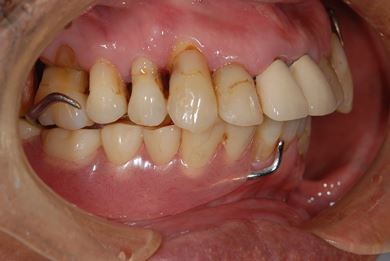

骨再生スピードインプラント治療+遊離歯肉移植

| 性別/年齢 | 男性 / 66歳 | ||||||||||||||||||||||||||||||||

| 主訴 | 入れ歯の部分をインプラントにしたい。 | ||||||||||||||||||||||||||||||||

| 治療方針 | サイナスリフトにより上顎洞を拳上し、インプラント治療を可能にする。 | ||||||||||||||||||||||||||||||||

| 治療内容 | インプラント8本(サイナスリフト、抜歯即日スピードインプラント)、ハイブリッドセラミッククラウン9本、遊離歯肉移植 | ||||||||||||||||||||||||||||||||